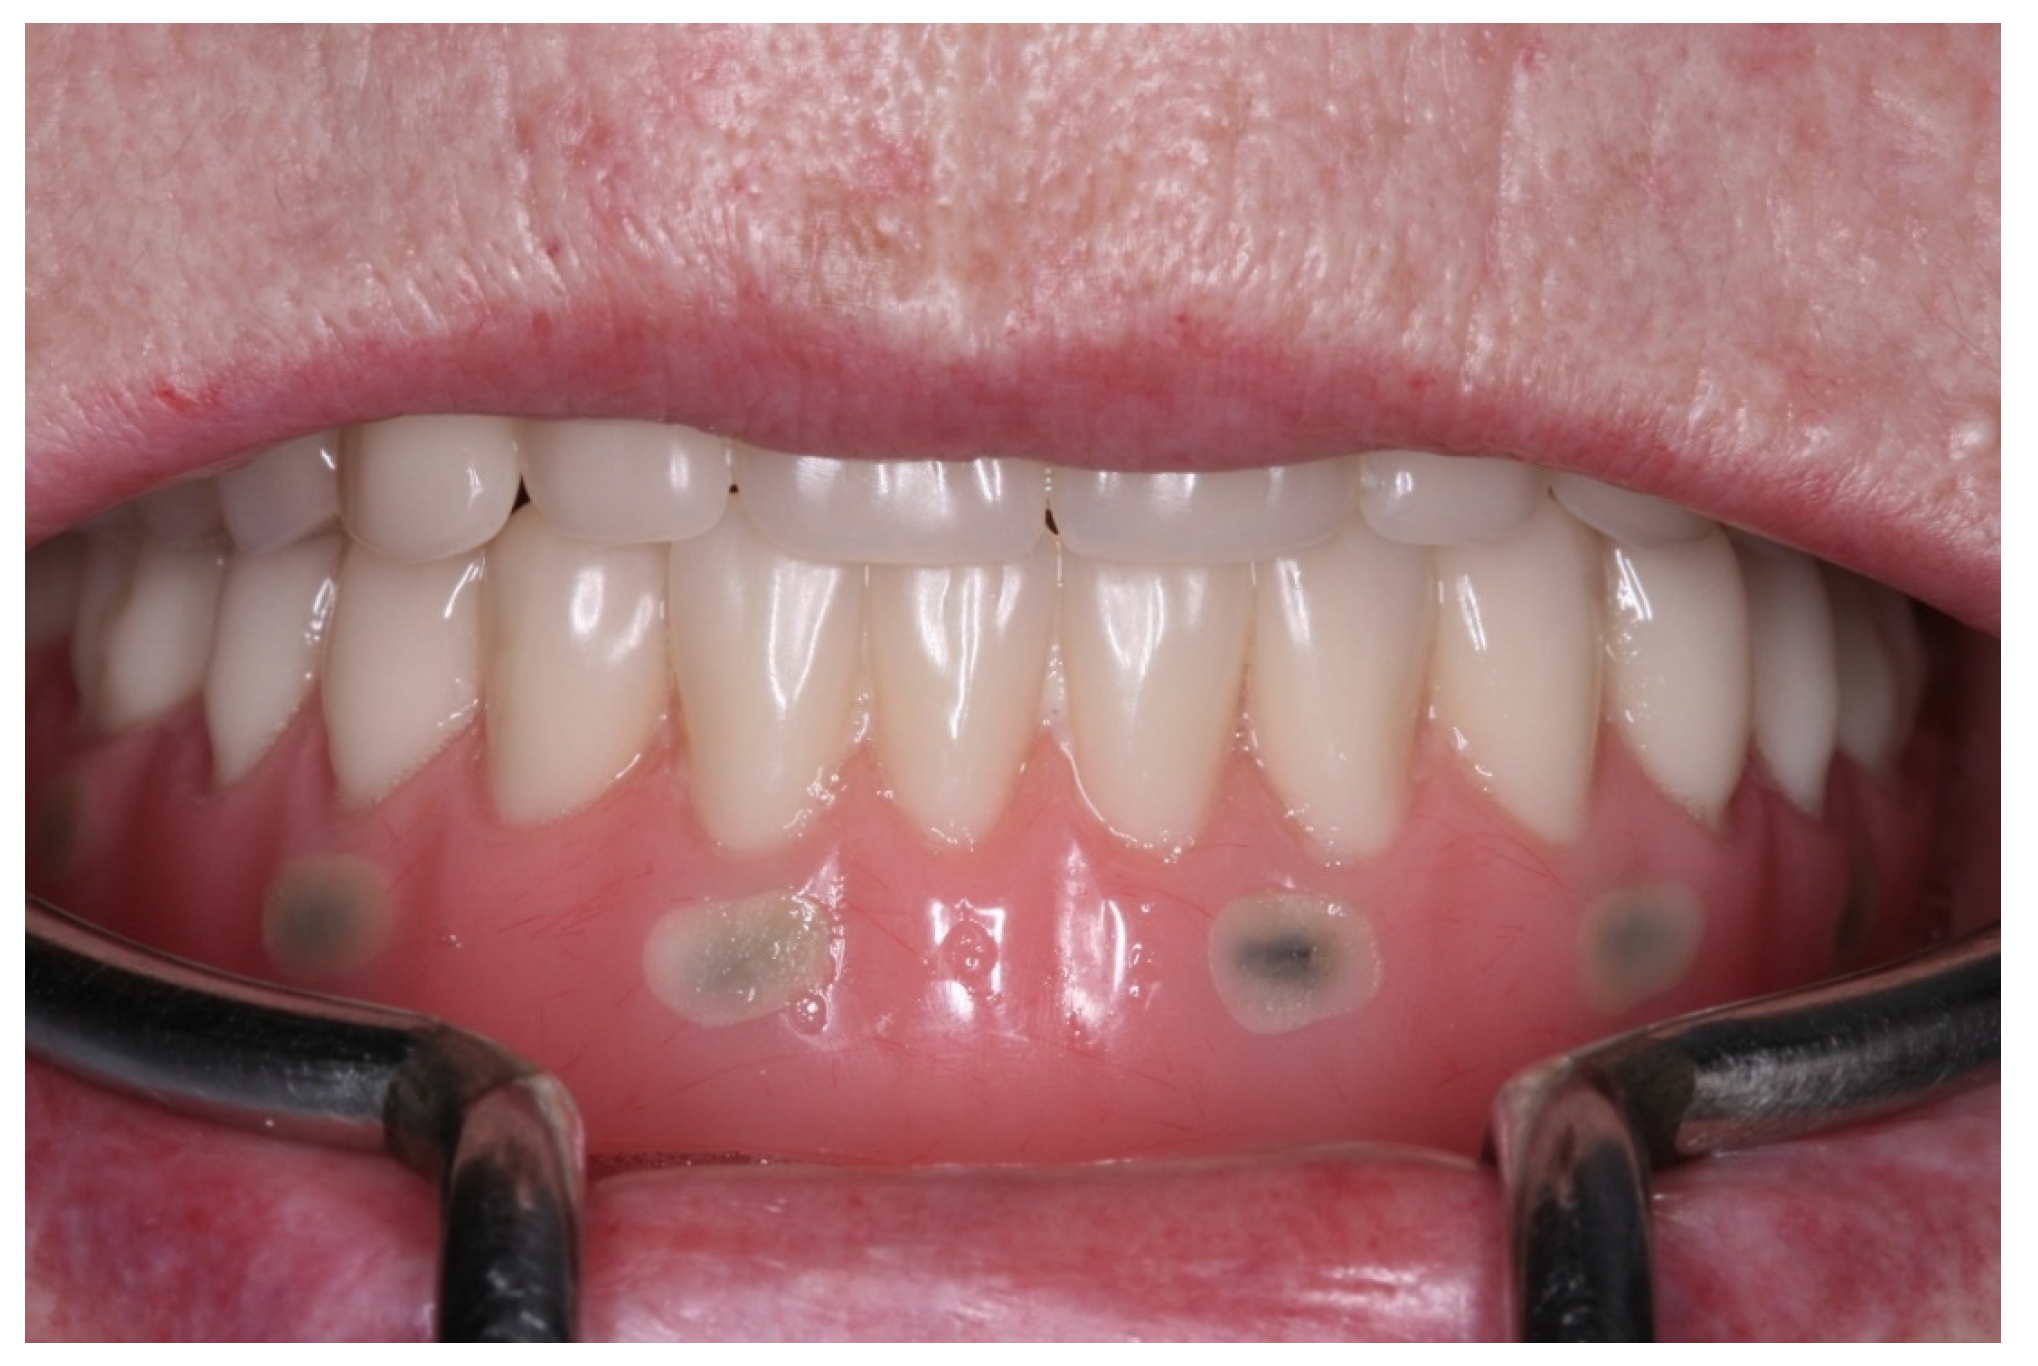

2. Case Report